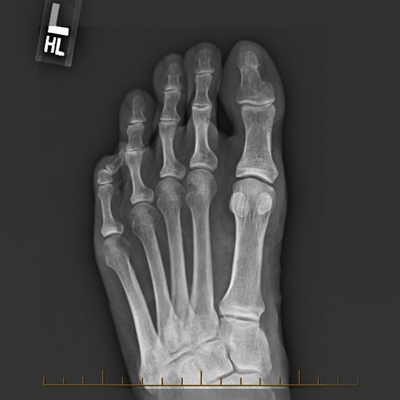

Click on an image below to view more info.